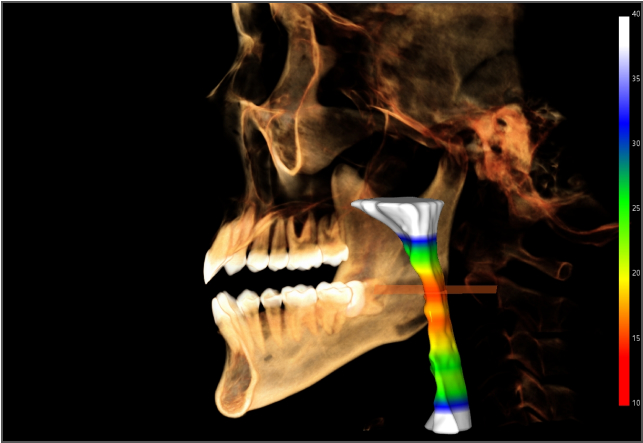

• lamtau 模擬種植

模擬種植

• lamtau AI氣道分析

AI氣道分析